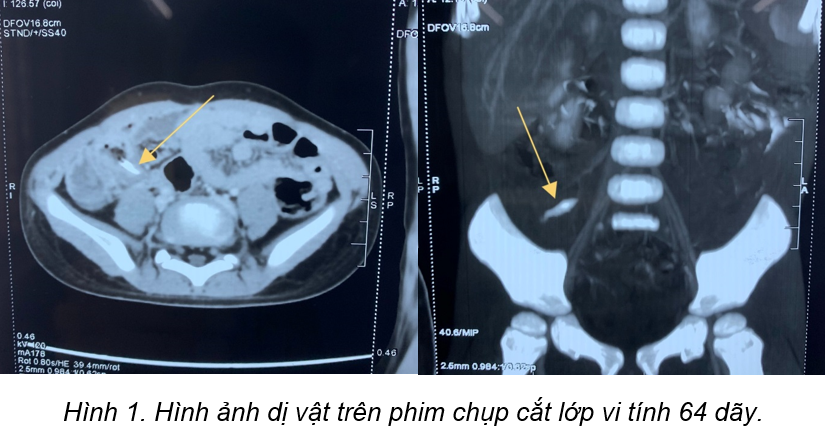

Qua thăm khám lâm sàng cho thấy bụng không chướng nhưng khi nắn

vùng hố chậu phải có phản ứng thành bụng, trên phim chụp X quang bụng không

chuẩn bị không thấy hình ảnh cản quang bất thường. Nhận định đây có thể là một

trường hợp bụng ngoại khoa, trẻ được chỉ định chụp cắt lớp vi tính ổ bụng, kết

quả cho thấy cháu bị thủng ruột non do dị vật nhọn, dài 2,5cm, xuyên thủng

thành đoạn cuối ruột non. Các bác sĩ Bệnh viện Trẻ em Hải Phòng đã chỉ định mổ